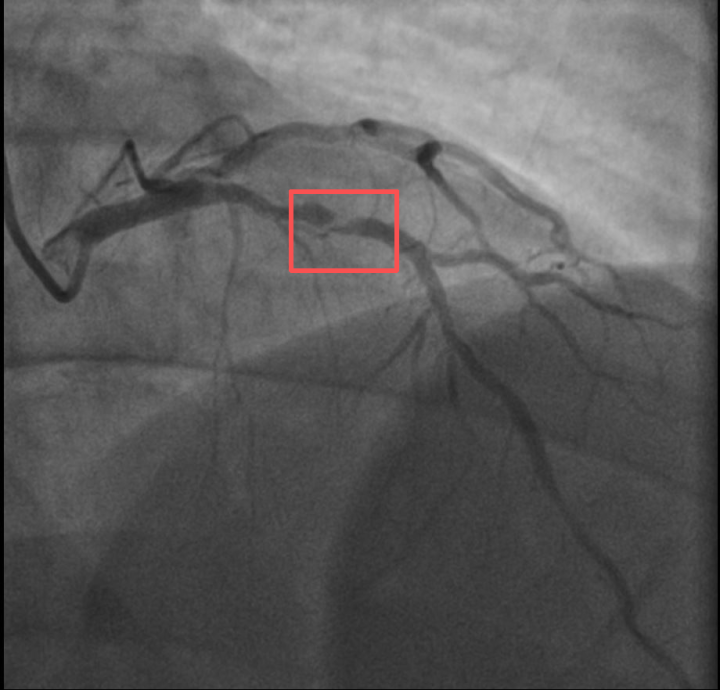

浙江医院心血管内科副主任汤益民主任医师分析,剧烈运动导致这位患者心脏的不稳定斑块破裂,进而造成前降支近段次全闭塞。所幸送医及时,接受紧急介入治疗后,孙先生的身体险情被成功化解。

介入治疗前后影像图